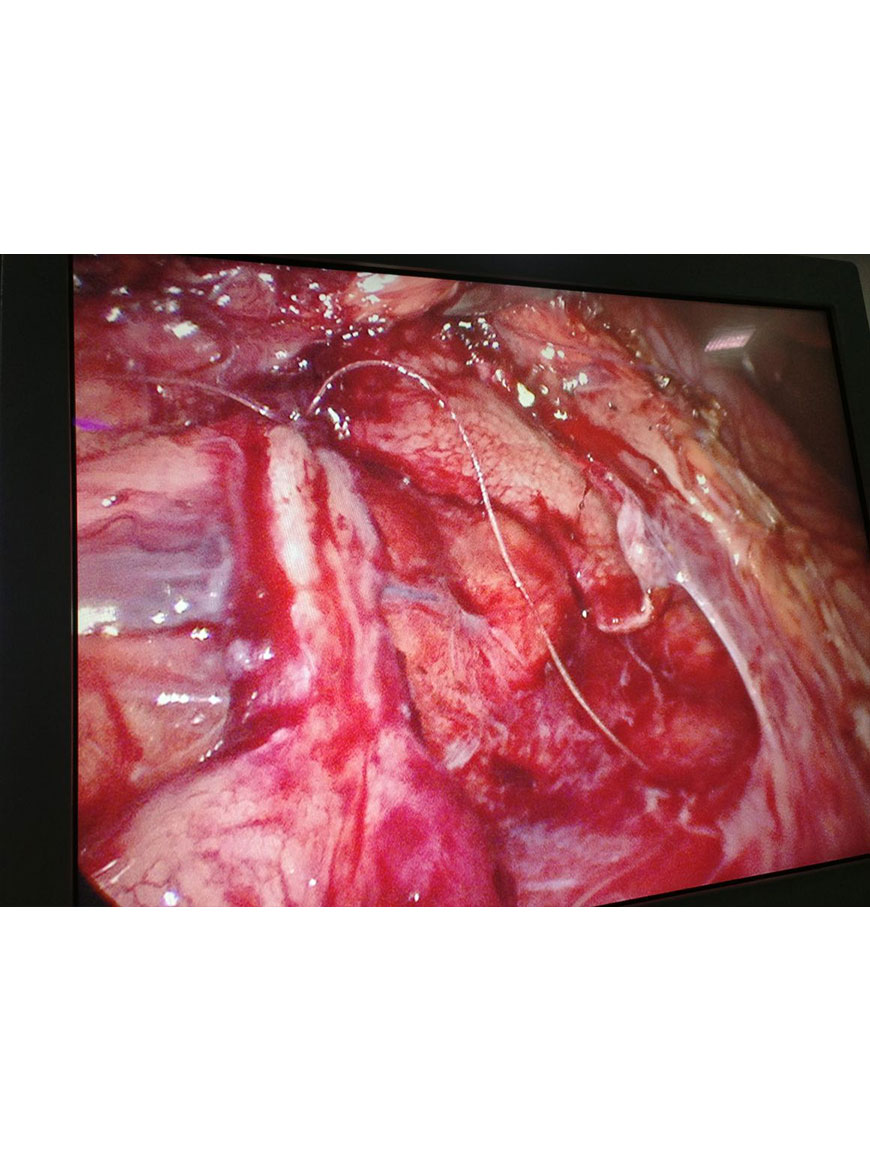

Lap Pyeloplasty